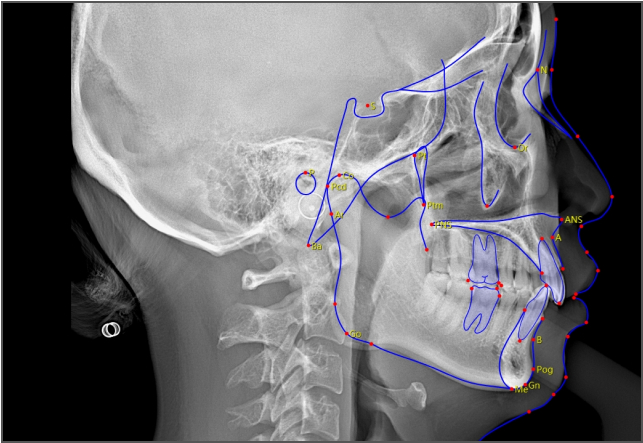

• lamtau AI頭影測量

AI頭影測量

單側頭影測量 專利 首創

偏頜患者的側位片左右側的影像不對稱,實際正畸測量時會產生較大的誤差。有方醫療推出單側頭影測量功能。這一功能有效解決了這一臨床問題,在口腔正畸領域廣受好評,并于2023年成功獲得國家發明專利授權。

單側頭影測量